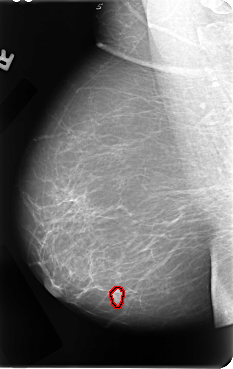

B_3067_1.RIGHT_MLO

RIGHT_MLO LINES 4792 PIXELS_PER_LINE 3024 BITS_PER_PIXEL 12 RESOLUTION 50 OVERLAY

FILE: B_3067_1.RIGHT_MLO.OVERLAY

TOTAL_ABNORMALITIES 1

ABNORMALITY 1

LESION_TYPE MASS SHAPE LOBULATED MARGINS CIRCUMSCRIBED-ILL_DEFINED

ASSESSMENT 4

SUBTLETY 4

PATHOLOGY MALIGNANT

TOTAL_OUTLINES 1